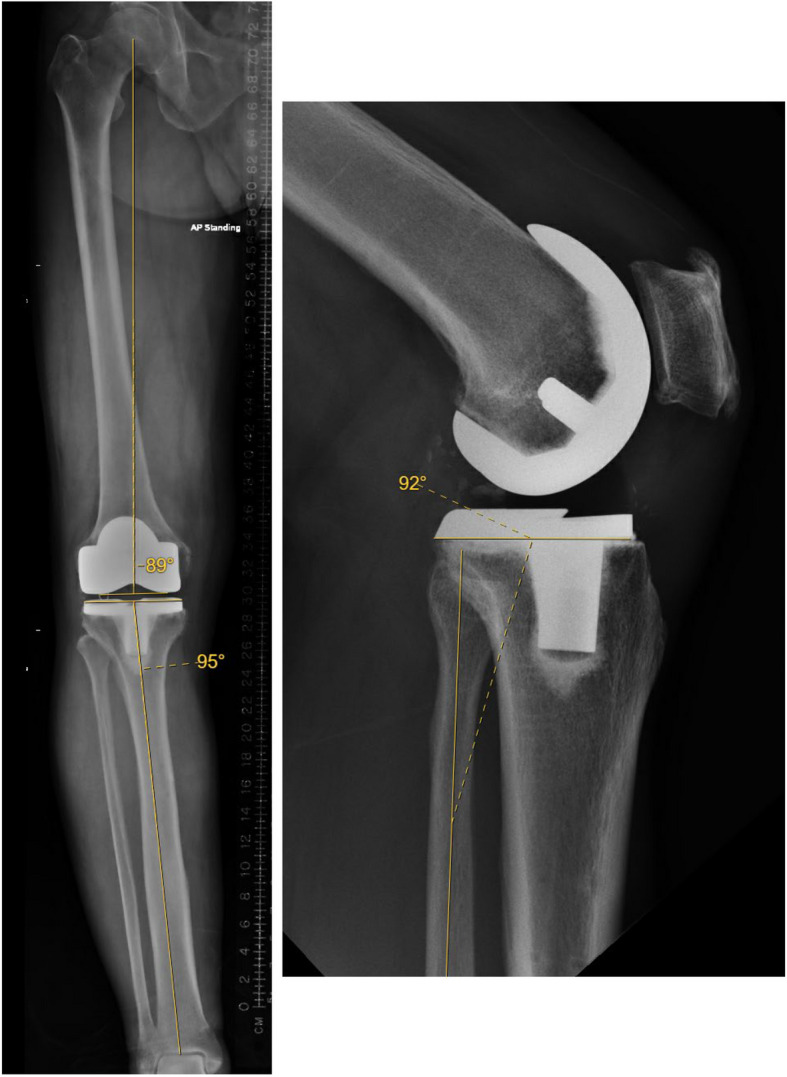

Methods: A multi-centre retrospective analysis of 129 robotic-assisted TKAs (Zhengtian Irene, n = 60; DePuy Synthes Attune, n = 32; Zimmer Biomet Persona, n = 20; Smith & Nephew Legion, n = 17) was conducted. Patients with end-stage osteoarthritis (Kellgren-Lawrence grade 3-4) were included, while those with prior knee surgery or complex anatomy were excluded (n = 15). A total of 114 pre-operative and post-operative alignment (hip-knee-ankle angle [HKA], femoral and tibial component coronal angles [FCCA, TCCA], posterior tibial slope [PTS]) were measured on radiographs by two independent reviewers. Interobserver reliability (intra-class correlation [ICC], Cronbach's α) and deviations from planned alignment (paired t-tests) were analysed. Acceptability was defined as ≤ 3° deviation.

Results: Interobserver reliability was excellent (ICC > 0.77, Cronbach's α > 0.87 for all parameters). Mean post-operative deviations from planned alignment were clinically small: HKA (+1.32°, P < 0.001), FCCA (-0.55°, P < 0.001), TCCA (+0.19°, P = 0.097), and PTS (-0.42°, P = 0.018). All mean differences were within the 3° acceptability threshold. Subgroup analysis of pre- and post-operative alignment between implant types also showed deviations of < 3°.